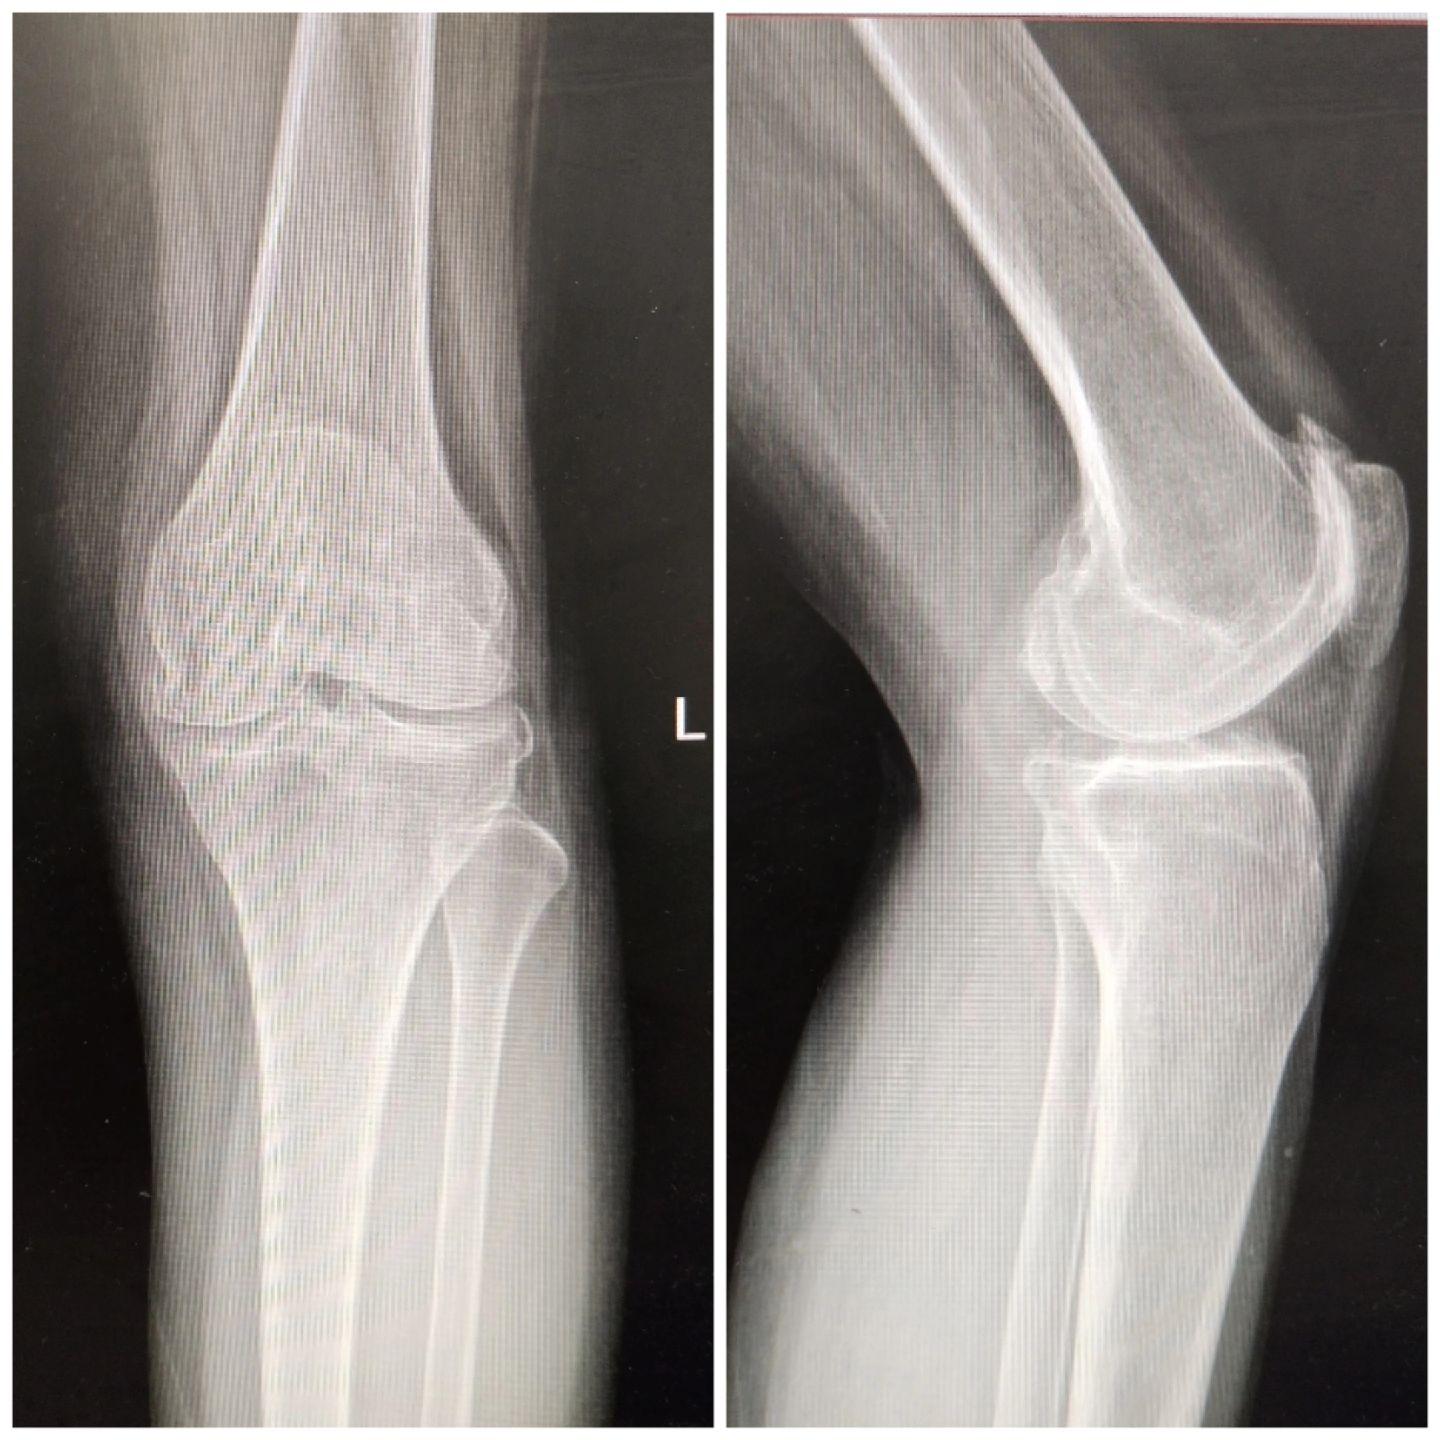

UKA单髁置换。膝关节骨关节炎,同期双侧单髁置换,术后四天出院,快速康复,省医关节外科🌹